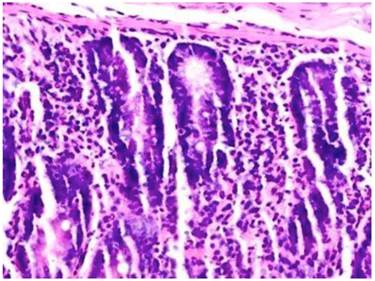

Figure 3

Duodenum of group C; Microscopic examination showed intra-epithelial lymphocyte infiltration (hematoxylin and eosin, x20).

In the group C rats, subjected to 3 months of oral ABS administration, inflammation, goblet cell loss and intra-epithelial lymphocyte infiltration were observed in all of the rats. Mixed inflammation included eosinophil, neutrophil and lymphocyte that were observed in the duodenum (50 %), jejunum (50 %), and caecum (66.6 %). Eosinophilic and neutrophilic inflammations of the rectum were also evident (100 %). Inflammations were observed in the mainly lamina propria. Loss of goblet cell reductions of 66 % in the duodenum and 100 % in the jejunum were detectable in this group with longest exposure to ABS. Intra-epithelial lymphocyte infiltration in the duodenum, jejunum and caecum were found in all of the rats in this cohort (group C). Control group (group D) did not demonstrate any pathological changes of the liver or gastrointestinal tract.

The magnitude and frequency of inflammation was greater in groups B and C in comparison to group A (P= 0.001). Loss of goblet cell and intra-epithelial lymphocyte infiltration were not significantly different between groups A and B (P= 0.308 and P= 0.189, respectively). However, there was significantly higher intra-epithelial lymphocyte infiltration in group C than in group A (P=0.04). The histopathological appearances and the parameters for the inflammation, loss of goblet cell and intra-epithelial lymphocyte infiltration are depicted in Table 1.